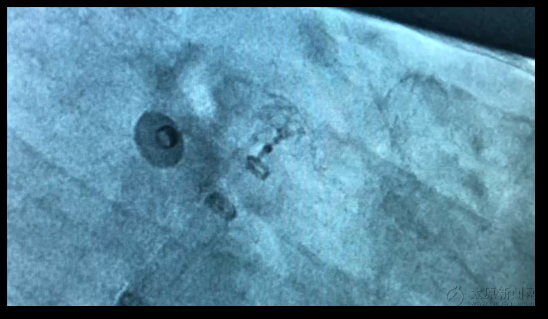

▲緩緩撤鞘,使封堵器緩緩原位展開。

▲即刻造影,封堵器位置略深。

▲再次造影封堵器達到理想位置,DSA下封堵完全。